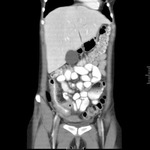

Doença associada ao Clostridium difficile: tomografia computadorizada (TC) do abdome mostrando espessamento macroscópico da parede do intestino grosso e obliteração do lúmen

Yates B, Murphy CM, et al. Pseudomembranous colitis in four patients with cystic fibrosis following lung transplantation. BMJ Case Reports. 2009; doi: 10.1136/bcr.11.2008.1218